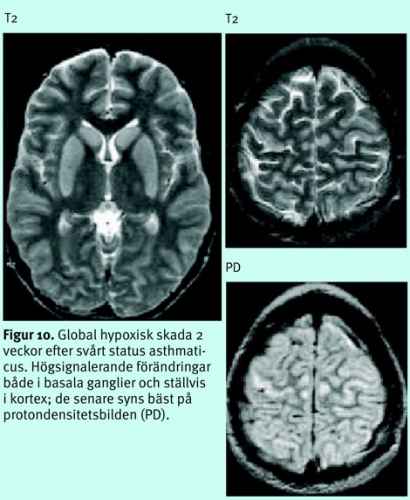

Diffus hjärnskada efter djup anoxi/hypoxi eller excessivt lågt systemblodtryck, tex efter hjärtstillestånd, status asthmaticus, kolmonoxidförgiftning, grav hypovolemi etc, ger, om den inte är letal, en selektiv skada på vissa neuronpopulationer, framför allt på dem med högst krav på energitillförsel, dvs i basala ganglier, i kortex känsligaste lager (3, 4 och 5), hippocampi, thalami mfl (Figur 10), ibland i watershed-områdena (Figur 11) [13].

Sedan decennier vet vi att skador av global ischemi ibland kan visualiseras med DT subakut och att de vanligen blir tydligare efter 3–4 dagar. Diffusionsviktade bilder är ett betydligt känsligare instrument för att påvisa globala hypoxiska/ischemiska förändringar, men den kliniska nyttan är ofta begränsad. Radiologen kan sällan infria intensivvårdsläkarens förhoppningar om säker prognostisk information om huruvida ett permanent vegetativt tillstånd är att vänta, eftersom någon entydig gräns mellan förändringar som kan vara förenliga med återhämtning och irreversibla skador inte finns, inte ens med denna teknik. Utbredda, kraftiga förändringar i basala ganglier kan dock ge en fingervisning om ett dåligt neurologiskt utfall.